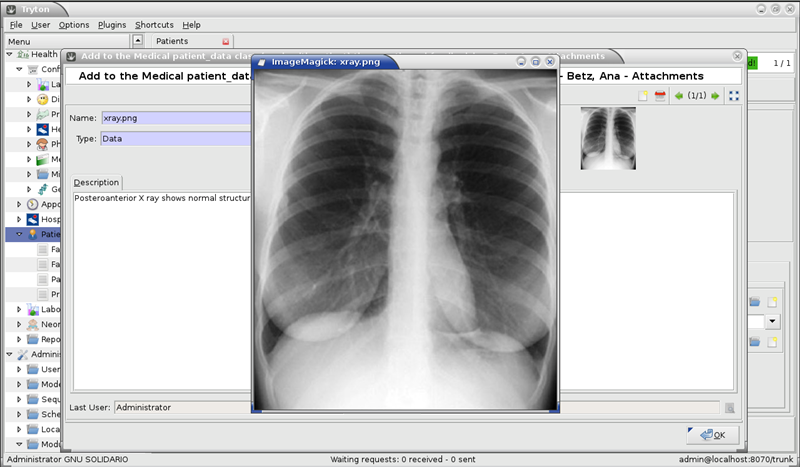

Fotogalerie: GNU Health

GNU Health (CC BY-SA 3.0)